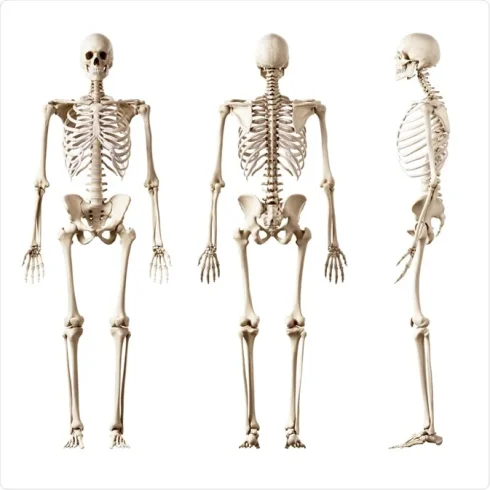

پروتئومیکس استخوان و کاربردهای آن

پروتئومیکس استخوان چیست؟ پروتئومیکس استخوان، یک مطالعه بر روی پروتئینهای موجود در ترکیبات استخوانی، برای[بیشتر بخوانید]